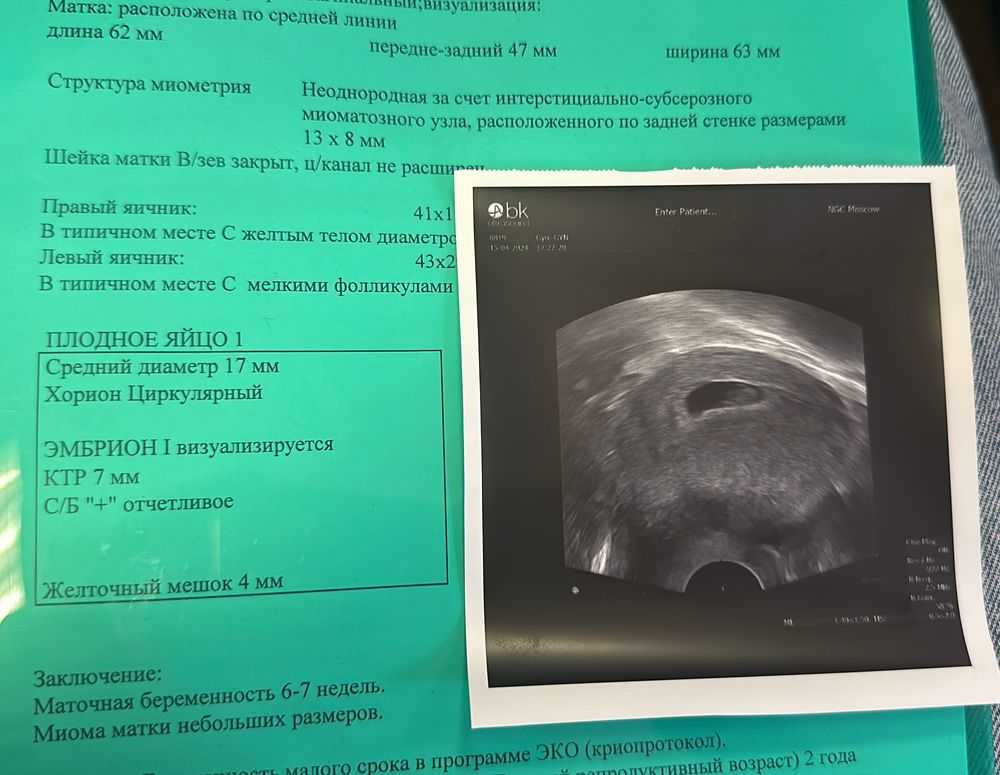

УЗИ, КТГ, доплерДевочки, 6 дней назад делала узи, ктр был 7мм, услышали чсс 122, жм 2.8.

Сегодня пошла вставать на учет, мне сделали узи и вот ктр всего 8 мм, разве может такое быть? ЧСС 156, жм 3.6. Я не понимаю как может всё вырасти кроме ктр? Спросила в врача, она мне сказала, что разные аппараты узи. Так напряглась, если честно…

IMPREGGY, вот такая крокозябра была в 7 недель, точно не точка. В любом случае, чсс у вас хороший, все у вас хорошо должно быть. Кто-то из узистов точно накосячил с замером или записал криво.

IMPREGGY, у вас прям домище по сравнению с моим пя)) если хотите заморочиться, можно пропорцией прикинуть

пя по узи-сколько см по фото

X ктр эмбриона-и замерить по фото

Ирина, по узи пя было 25, ктр 7. Если примерно прикинуть, то все выходит верно. Сегодня мне ПЯ не мерили вообще, но он уже не казался мне таким огромным.